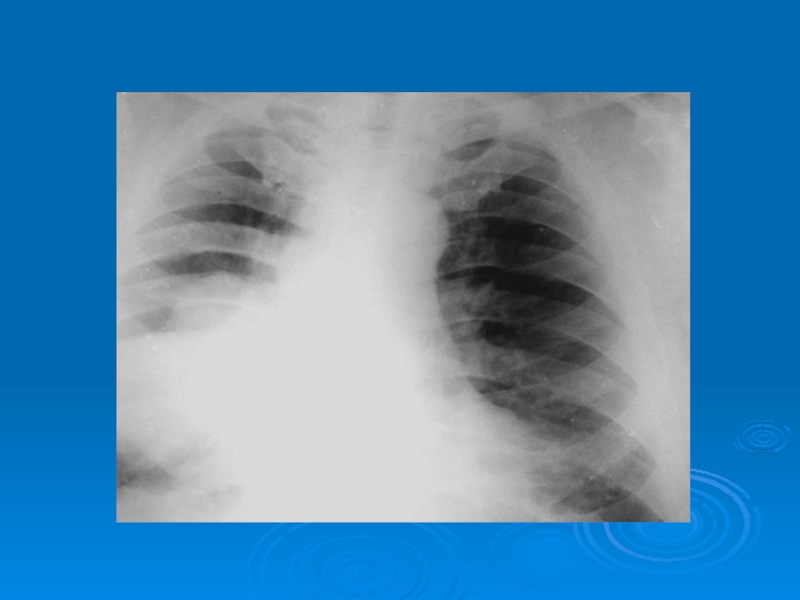

Слайд 43Распространенные диффузные диссеминации (метастазы злокачественной опухоли)

Распространенные диффузные диссеминации (метастазы злокачественной опухоли)